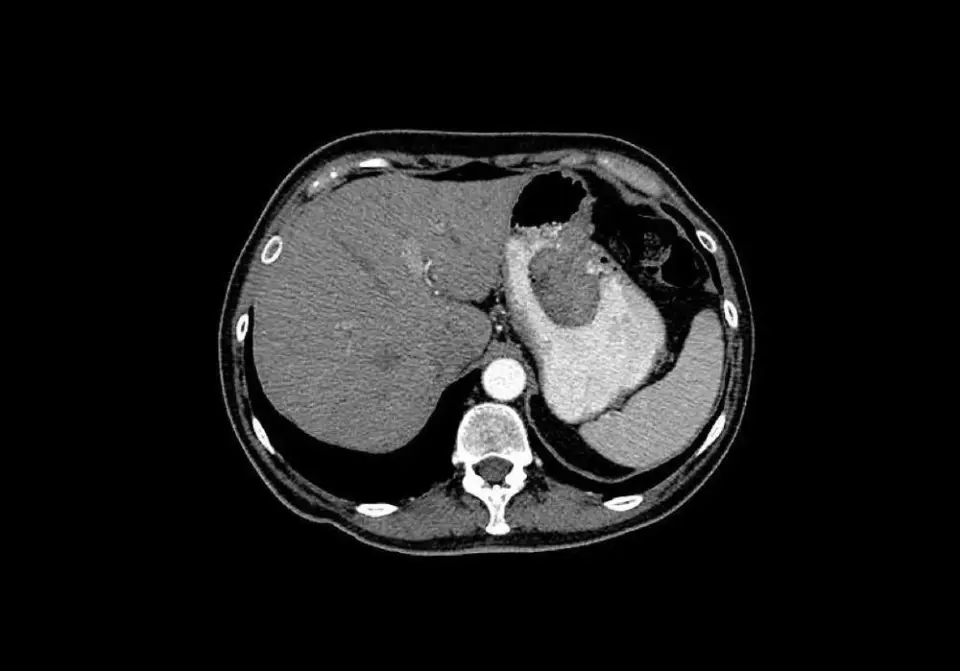

Aflatoxin trong ngũ cốc và quả hạch bị mốc là một trong những chất gây ung thư hóa học mạnh nhất được biết đến, đặc biệt liên quan chặt chẽ đến sự xuất hiện của ung thư gan.